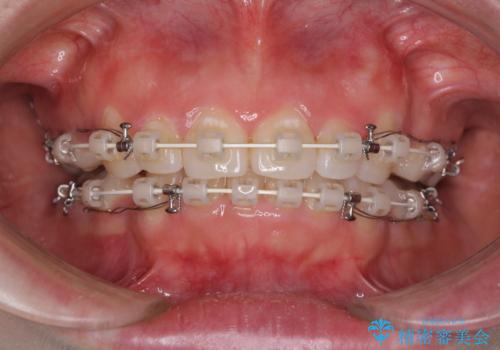

- 矯正装置

- 審美装置

当初は口元の突出感はあまり気にされていない様子だったので、インビザラインによる非抜歯矯正をお勧めしたが、ふっくらとした口元を改善したいとのことで、積極的に口元の突出感を改善することとしました。

上下左右第一小臼歯4本の抜歯を行い、ワイヤー装置による矯正治療を行うこととしました。

元々上下正中の位置はずれていましたが、治療中によりズレが大きくなったので、元の位置に戻すため治療期間を余計に要しました。